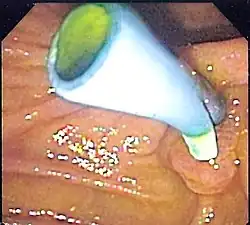

The placement of a colon stent involves endoscopic techniques similar to esophageal stenting. A thin tube called an endoscope is inserted into the rectum and guided through the colon to locate the blockage. Using fluoroscopy or endoscopic guidance, a guidewire is passed through the narrowed area and then removed after positioning it properly. The stent is then delivered over the guidewire and expanded to keep open the obstructed section of the colon. Complications associated with colon stents include perforation of the intestinal wall, migration or dislodgment of the stent, bleeding, infection at insertion site, or tissue overgrowth around it.[10]